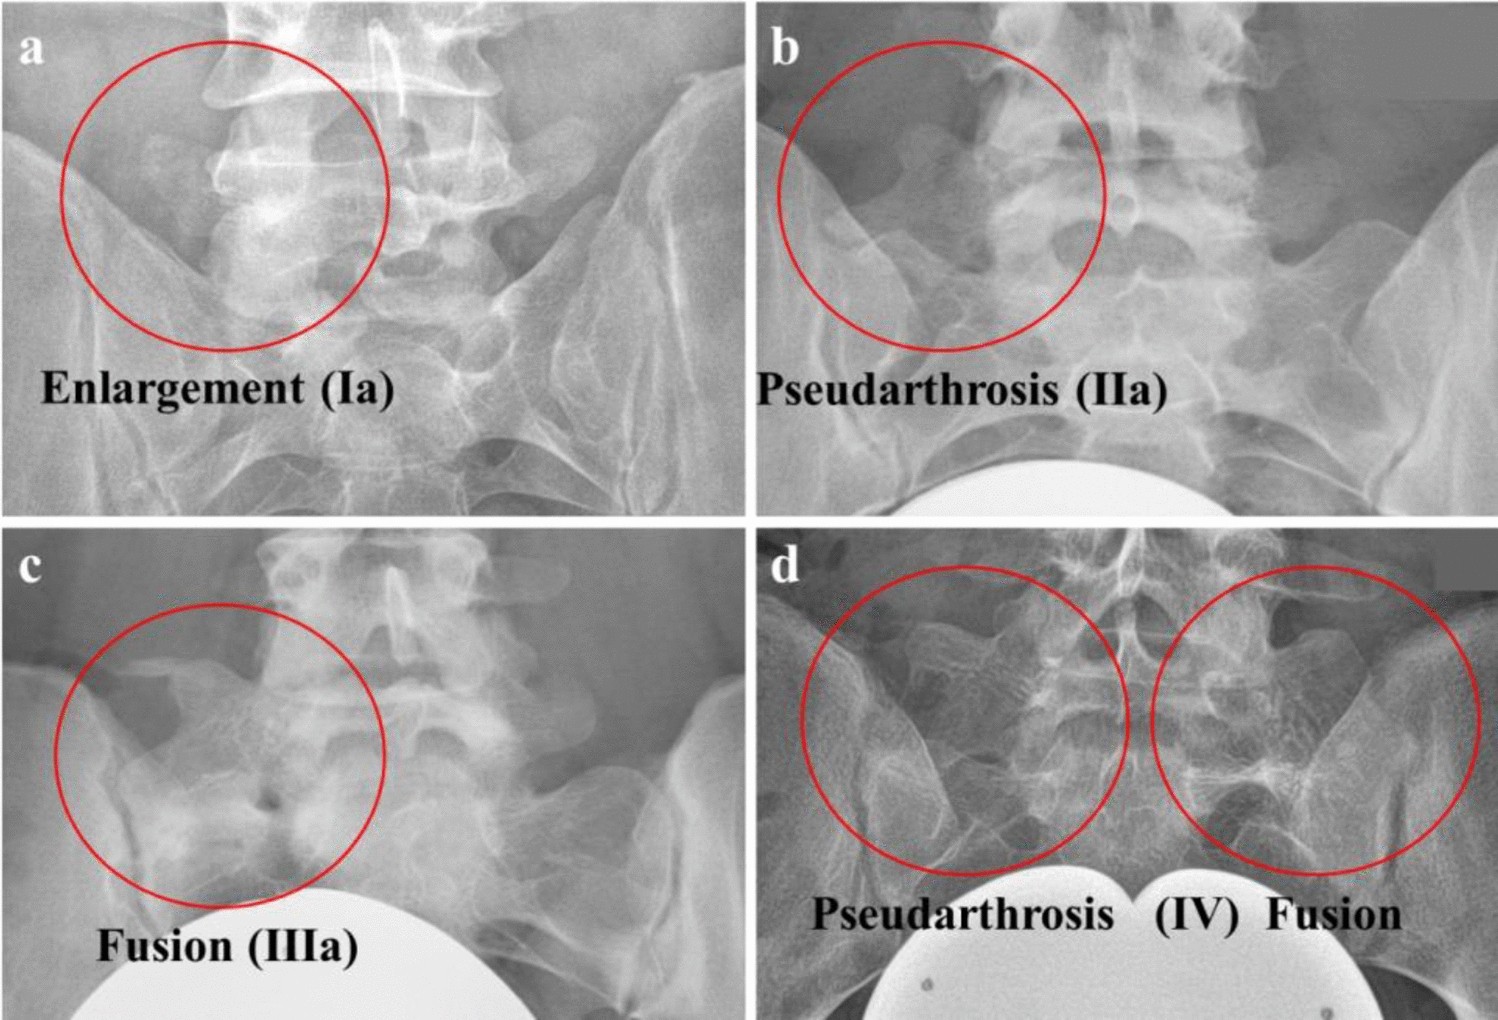

Figure 2

Classification of patients with LSTV according to Castellvi12 Dysplastic enlargement of the transversal process > 19 mm was classified as Castellvi Ia (a) if it appeared unilateral and as Castellvi Ib if it was detected bilateral. Patients with unilateral (IIa) (b) or bilateral (IIb) pseudarthrosis of the transversal process with the sacral ala were classified as Castellvi II. Patients with unilateral (IIIa) (c) or bilateral (IIIb) osseous fusion of the transversal process with the sacral ala were classified as Castellvi III. Patients with unilateral pseudarthrosis and contralateral osseous fusion were classified as Castellvi IV (d).